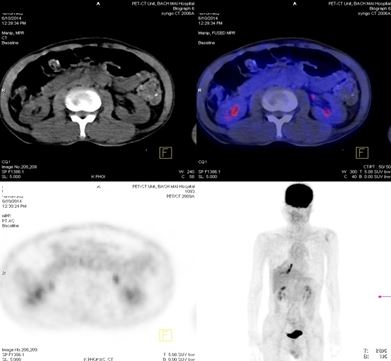

-          Bệnh nhân đã được tiến hành chụp PET/ CT đánh giá, kết quả:

+ Vùng phế quản gốc phải có khối KT 2,4x1,7cm, tăng hấp thu F-18 FDG, max SUV=8,50. Hạch trung thất kích thước lớn nhất 3,1x3,5cm, max SUV=10,29

+ Hạch thượng đòn phải KT 1,1cm, tăng hấp thu F-18 FDG, max SUV=5,67; Hạch thượng đòn trái KT 0,8cm, max SUV=3,97. Tổn thương cung sau xương sườn số 2 bên phải tăng hấp thu F-18 FDG, max SUV=3,13.

+ Nhiều hạch ổ bụng dọc theo ĐM chủ bụng tạo thành khối lớn KT 8,5x5,1 cm và 5,1x3,9cm, tăng hấp thu F-18 FDG, max SUV=10,45. Nhu mô gan hạ phân thùy VI có nốt KT 1,2cm, tăng hấp thu F-18 FDG, max SUV=4,15.

-Trước điều trị: Nhiều hạch ổ bụng dọc theo ĐM chủ bụng tạo thành khối lớn KT 8,5x5,1 cm và 5,1x3,9cm,  max SUV=10,45.

-Sau điều trị 4 tháng: Không có hạch ổ bụng